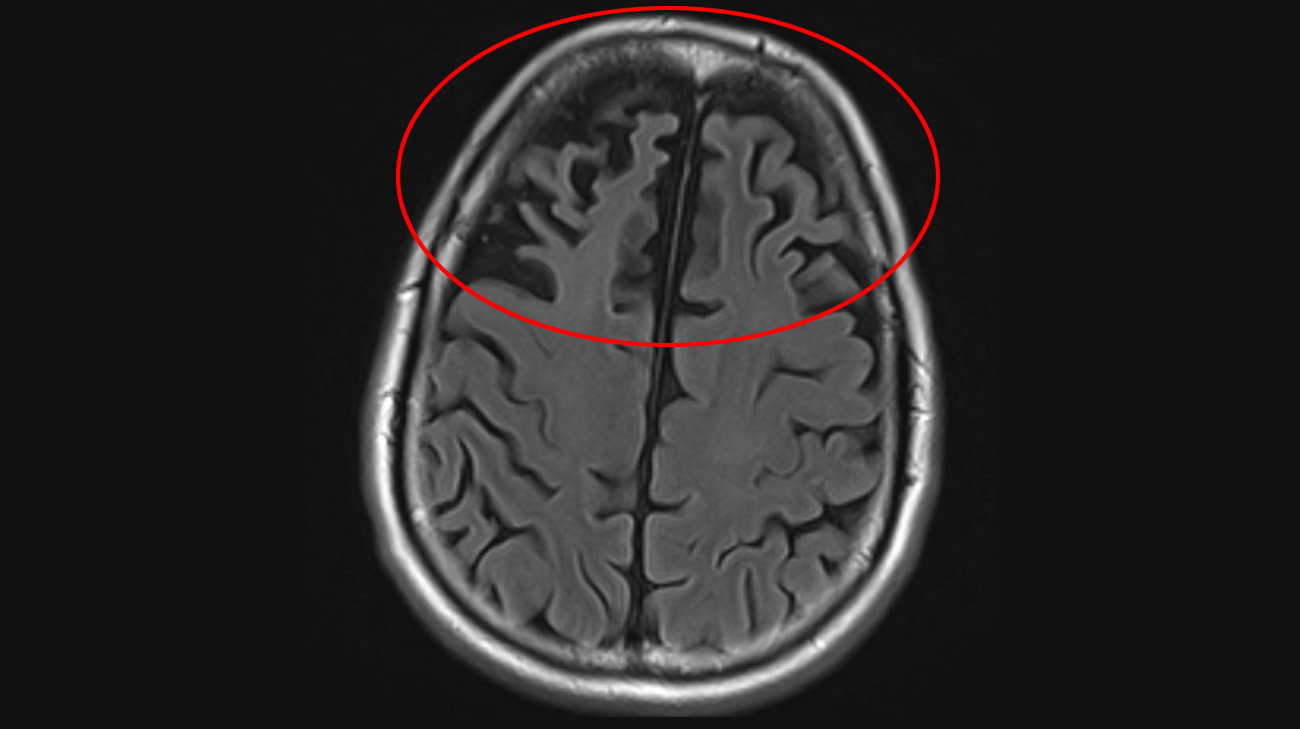

Sean's MRI showed frontal lobe atrophy, or shrinkage, a finding commonly associated with frontotemporal dementia (FTD). (Courtesy: Cleveland Clinic)

“I saw the picture of my MRI up on the screen, and it didn’t look good to me. I was shocked and didn’t really know what to think when he said it was FTD,” says Sean, recalling the day he was diagnosed with the disease at 57 years old in March 2024.